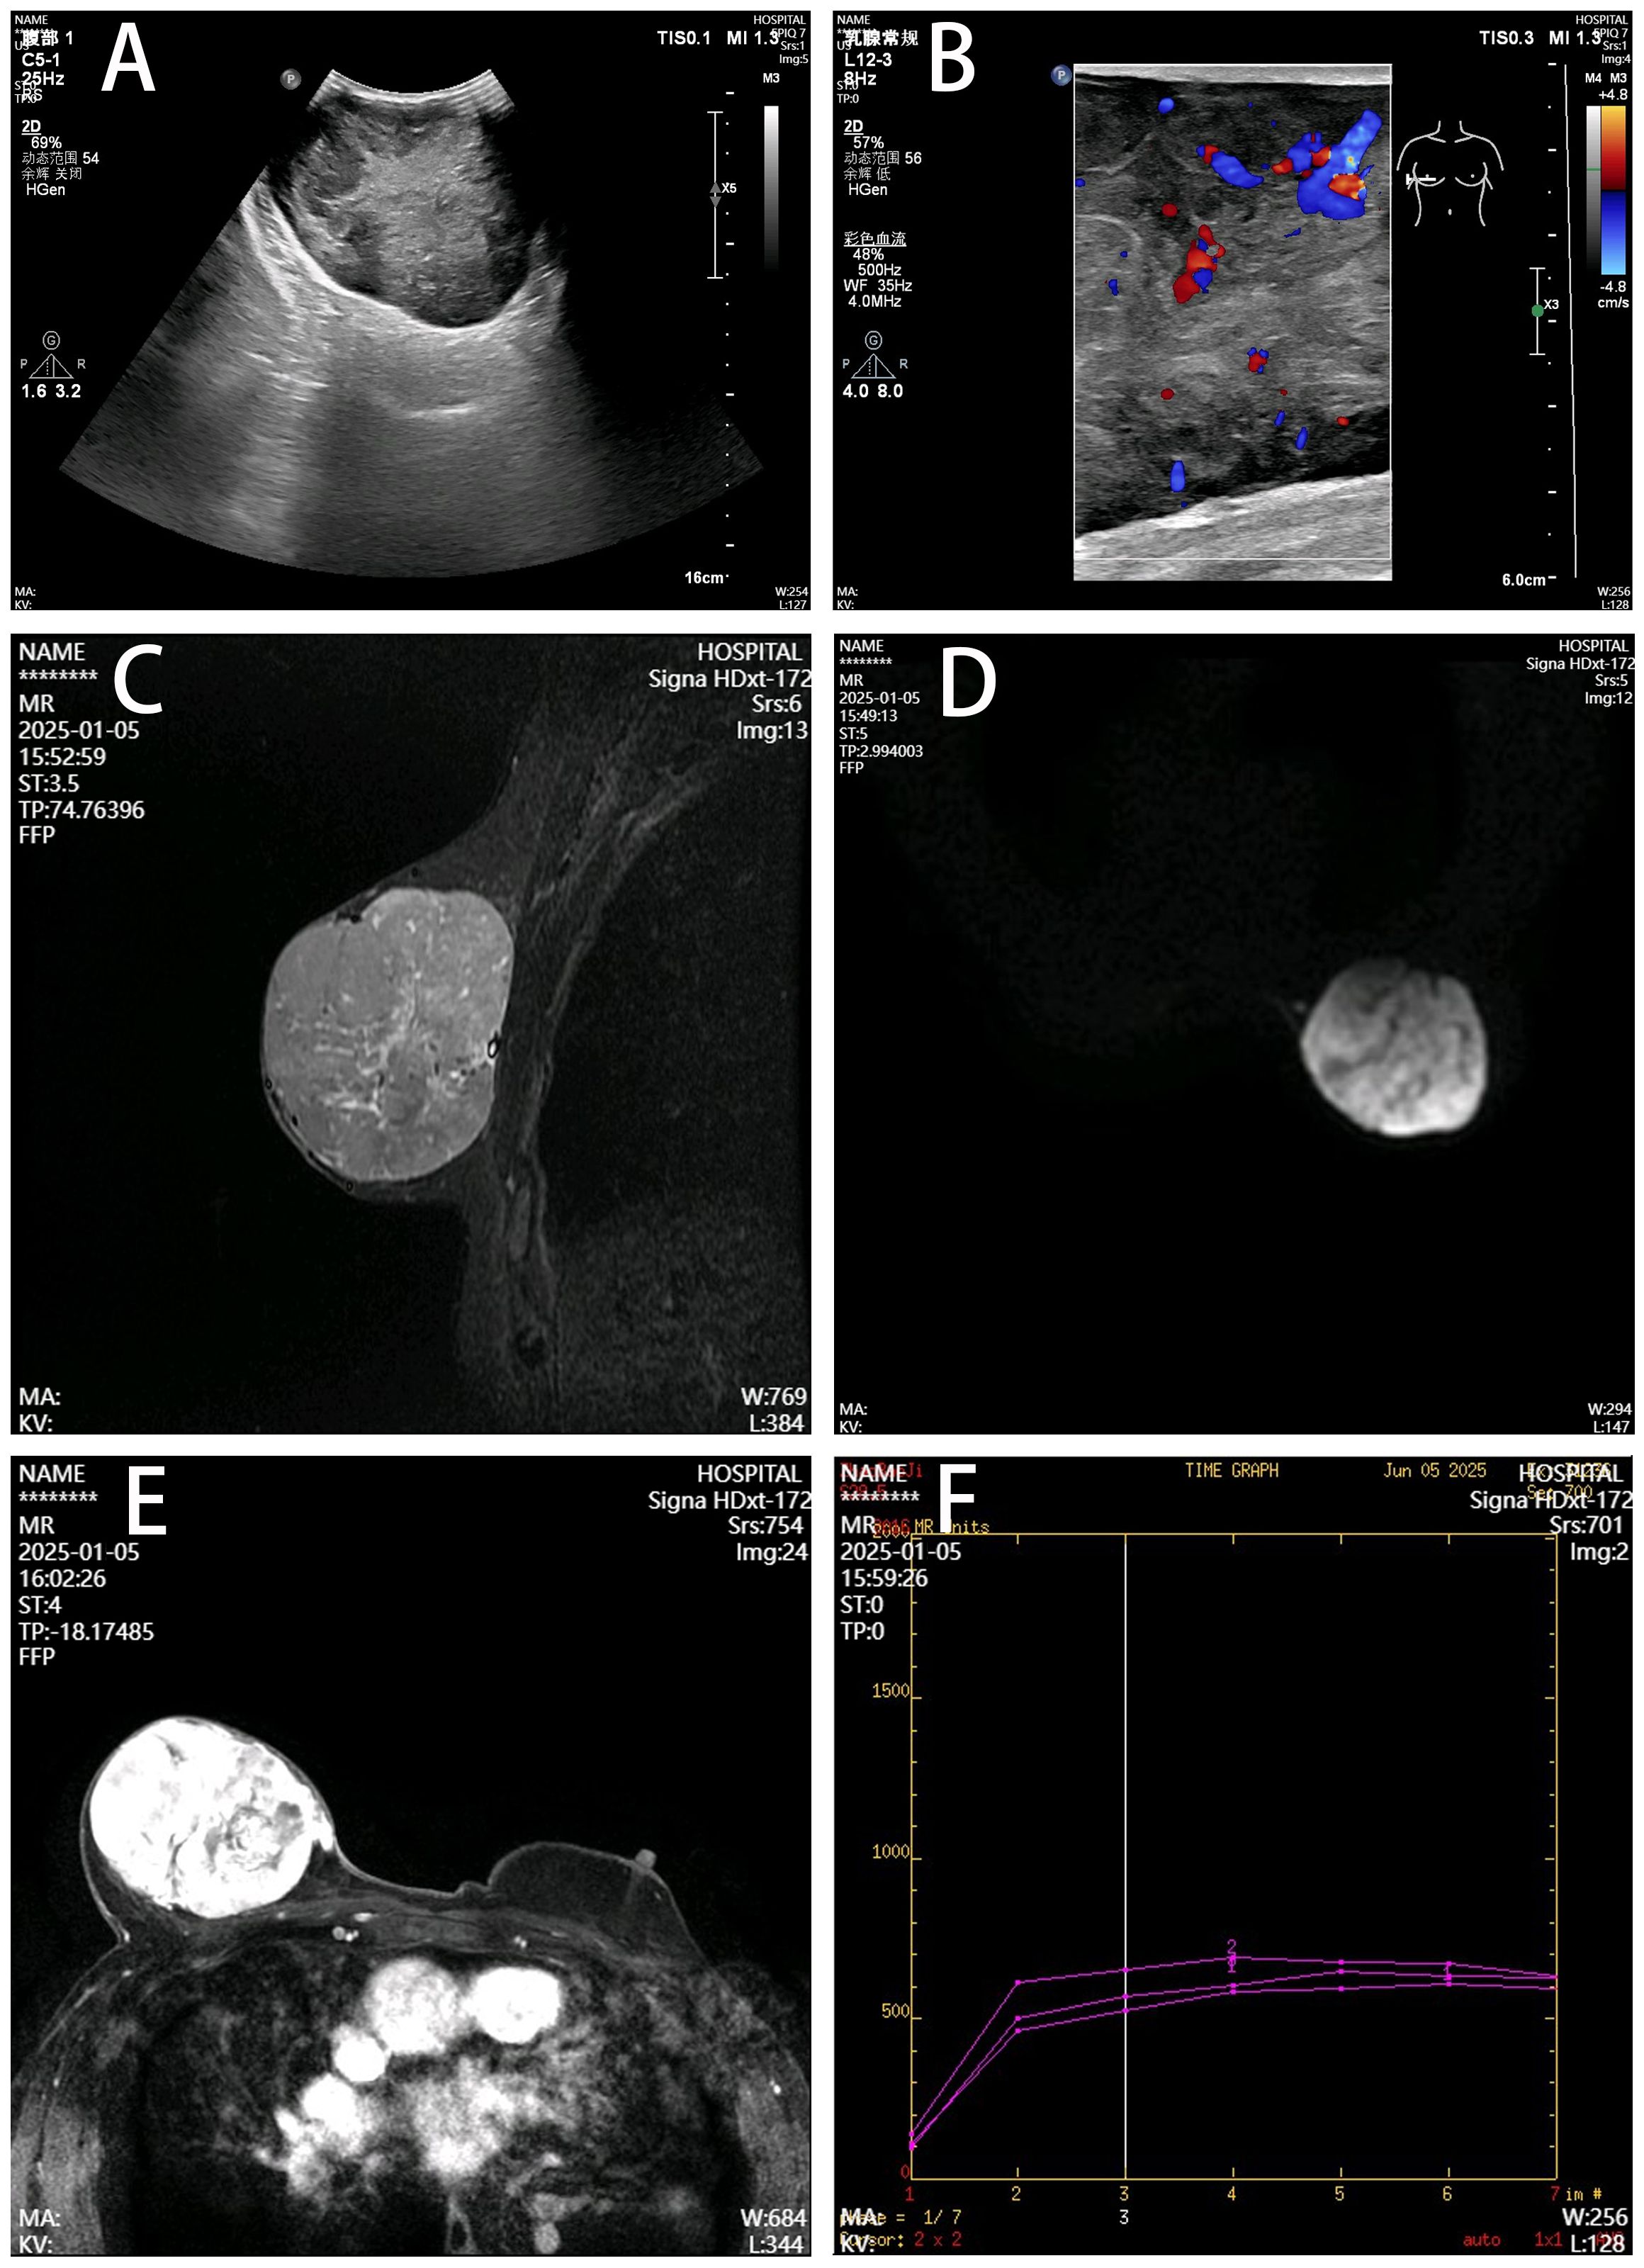

Breast ultrasonography revealed a 123 mm × 94 mm × 55 mm hypoechoic mass with well-defined margins and relatively rich internal blood flow signals in the right breast region, assessed as BI-RADS category 4a. Magnetic resonance imaging (MRI) demonstrated a large right breast mass showing T1 hypointensity and heterogeneous slight hyperintensity on T2 fat-suppressed sequences, measuring 9.2 cm × 7.2 cm × 7.1 cm. Contrast-enhanced scan exhibited marked heterogeneous enhancement with a rapid initial rise followed by plateau-type time-intensity curve (TIC) kinetics (Figure 2). Tumor markers (CA153, CA125) were within normal limits. Chest, abdominal, and pelvic computed tomography (CT) showed no evidence of metastasis.

Figure 2. Imaging features of the right breast mass. (A) Ultrasonography, Well-defined hypoechoic mass (12.3×9.4×5.5 cm) with heterogeneous echogenicity. (B) Color Doppler, Moderately abundant internal blood flow. (C) T2 fat-suppressed MRI, Lobulated mass showing heterogeneous hyperintensity (arrow). (D) DWI, Hyperintense signal with clear margins. (E) Contrast-enhanced MRI, Marked heterogeneous enhancement with capsular discontinuity (arrowhead). (F) Time-intensity curve, Rapid initial rise followed by plateau kinetics.